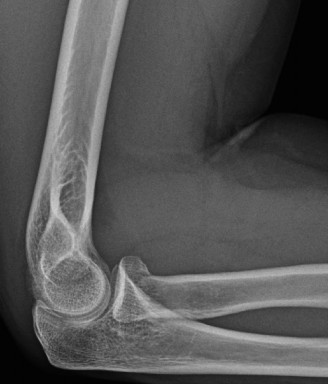

Treat a patient with infected total shoulder arthroplasty? CASE 21 A 70-year-old, right-hand-dominant female presents to clinic complaining of 4 years of gradually worsening chronic right shoulder pain and stiffness. She says the pain is worse at night and with any range of motion, denies a history of trauma, pain in other extremities, or numbness or tingling of the right upper extremity. She notes that her mother suffered from rheumatoid arthritis that affected her shoulder. Physical examination reveals decreased muscle bulk over the right supra- and infraspinatus fossae compared to the contralateral side, limited active and passive ROM, marked weakness with external rotation, and 4+/5 strength with shoulder abduction. X-rays of the right shoulder are shown in Figures 2–58 and 2–59.

Figure 2–58

Figure 2–59

The correct answer is (C). Rotator cuff tear arthropathy consists of a combination of rotator cuff insufficiency, glenohumeral joint degenerative changes, and superior humeral head migration. It is more common in women and also more often found on the dominant side. The patient’s clinical examination with weakened external

rotation and muscle atrophy signaling incompetent supra- and infraspinatus muscles point to rotator cuff insufficiency, and her plain films reveal narrowed glenohumeral joint space as well as superior migration of the humeral head. Choice D is incorrect because, while radiographs would show narrowing of the glenohumeral joint space, they would also likely show numerous osteophytes and posterior wear of the glenoid. Choice B is incorrect because, while adhesive capsulitis does present as decreased active and passive range of motion, the patient’s constellation of symptoms pointing towards rotator cuff insufficiency along with the radiographs make cuff tear arthropathy the more likely choice. Finally, Choice A is incorrect because even though she has a positive family history of rheumatoid arthritis, it is less likely to present only in a single joint. Also, rheumatoid arthritis on radiography appears more as an erosive process without the characteristic superior migration of the humeral head.

The correct answer is (A). Superior migration of the humeral head would be most indicative of chronic rotator cuff insufficiency associated with cuff tear arthropathy, as it is a direct result of the inability of the rotator cuff tendons to help maintain the humerus in its normal position. Acetabularization of the undersurface of the acromion is commonly associated with superior migration of the humeral head found in rotator cuff tear arthropathy, and can be assessed using the Hamada classification, which is based on measurements of the acromiohumeral interval on radiography (Table 2–8). Choices B and C are incorrect because, while narrowed glenohumeral joint space and subchondral sclerosis are associated with rotator cuff arthropathy on radiographs, they indicate degenerative joint changes rather than chronic rotator cuff insufficiency. Choice D is incorrect because it is not a specific sign of rotator cuff arthropathy.